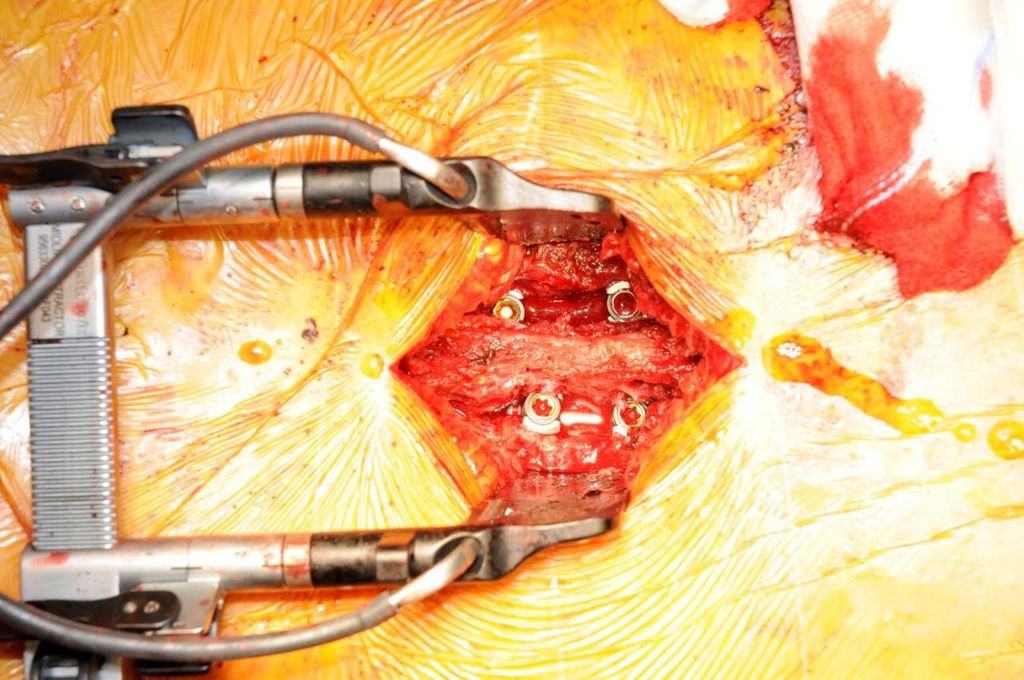

Bei der Implantation von Pedikelschrauben handelt es sich um den verbreitetsten Einsatz der Navigation in der Wirbelsäulenchirurgie. Es existieren unterschiedliche navigationsgestützte Techniken zur Implantation von Pedikelschrauben. So kann etwa eine Jamshidi-Nadel navigiert eingesetzt und anschließend können über Führungsdrähte die Schrauben eingebracht werden. Alternativ lässt sich der Schraubendreher selbst navigieren, wobei die geplante Schraubenlage im System visualisiert wird. Eine weitere Möglichkeit besteht im Vorbohren der Schraubenkanäle mittels navigierter Hochgeschwindigkeitsfräse. Je nach Hersteller und verwendetem Navigationssystem stehen somit verschiedenste Workflow-Varianten zur Verfügung. In zahlreichen Studien konnten eine höhere Genauigkeit und Sicherheit der Navigation im Vergleich zu konventionellen Methoden wie Freihandtechnik oder Durchleuchtung gezeigt werden. Eine Metaanalyse mit 14 Studien, 1723 Patient:innen und 9019 Pedikelschrauben zeigte eine signifikant geringere Fehlplatzierungsrate bei computergestützter Navigation (relatives Risiko 0,33) verglichen mit Fluoroskopie. Gleichzeitig wurden eine geringere intraoperative Blutungs- und Komplikationsrate dokumentiert, obwohl die Operationszeit mit Navigation im Durchschnitt länger war.5 Eine weitere große Metaanalyse über 24000 Schrauben fand heraus, dass 96,2% der Schrauben in der Navigationsgruppe klinisch akzeptabel platziert wurden – gegenüber 94,2% der konventionellen Methoden. Vor allem waren postoperative Revisionen und Komplikationen in der Navigationsgruppe signifikant reduziert.6 Auch eine systematische Übersicht über die zervikale Pedikelschraubenplatzierung dokumentierte signifikant niedrigere Fehlplatzierungsraten (12,5% vs. 18,8%) und komplikationsbedingte neurovaskuläre Schäden (0,3% vs. 1,9%) mit Navigation gegenüber Durchleuchtung.7 Gewisse Techniken, wie z.B. zervikale Pedikelschrauben, haben erst durch die Navigation einen entsprechenden Aufschwung erfahren. So implantieren wir beispielsweise an unserer Klinik seit 5 Jahren standardmäßig zum Großteil (subaxiale) zervikale Pedikelschrauben. Deren Vorteil ist der deutlich stärkere Halt der Schrauben, mit einer bis zu vierfach höheren „pull-out strength“ im Vergleich zu Massa-lateralis-Schrauben.8 Kleine Pedikel, die Nähe zur A. vertebralis und zur Nervenwurzel bzw. zum Myelon und die auch intraoperativ mobile HWS erschweren hingegen die Implantation. Auch bei routinemäßigem Einsatz kam es bisher bei mehr als 1100 implantierten zervikalen Schrauben zu keinem einzigen Fall einer Vertebralisverletzung oder einer schraubenassoziierten Verletzung von Spinalnerv oder Rückenmark. Auch postoperative Revisionen aufgrund einer Schraubenfehllage waren nicht notwendig.9

Beispiel für die Implantation zervikaler Pedikelschrauben. In diesem Fall kam es bei einem 61-jährigen Patienten 10 Jahre nach anteriorer zervikaler Diskektomie und Fusion (ACDF) C4/5 und ventraler Verplattung C4–6 zu einer Ankylosierung auch von C6/7. Nach Sturz kam es zu einer Fraktur bei C6/7 mit begleitender Bogenfraktur und auch Beteiligung der dorsalen Ligamenta (Abb. 1 und 2). Klinisch bestanden ausgeprägte Nackenschmerzen und kein neurologisches Defizit. Es wurde die Indikation der dorsalen Verschraubung von C4 auf Th1 gestellt. Intraoperativ wurde routinemäßig zusätzlich eine kleine Referenzschraube in einer Lamina – entfernt von der Dornfortsatz-Referenzklemme für die Navigation – gesetzt. Mit dieser konnte intraoperativ die Genauigkeit der Navigation exakt überprüft werden (Abb. 4 und 5). Mittels navigierter High-Speed-Fräse wurden die Schraubenkanäle vorgebohrt (Abb. 6), im Anschluss wurde der Bohrkanal ausgetastet und die Schrauben wurden implantiert. Abbildung 7 zeigt eine Röntgenkontrolle 3 Monate postoperativ.